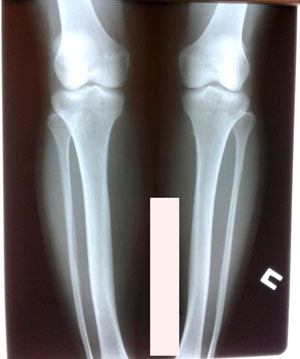

Исходник - 28 лет. Якутия.

Дата операции - 12.07.2019г.

подружки